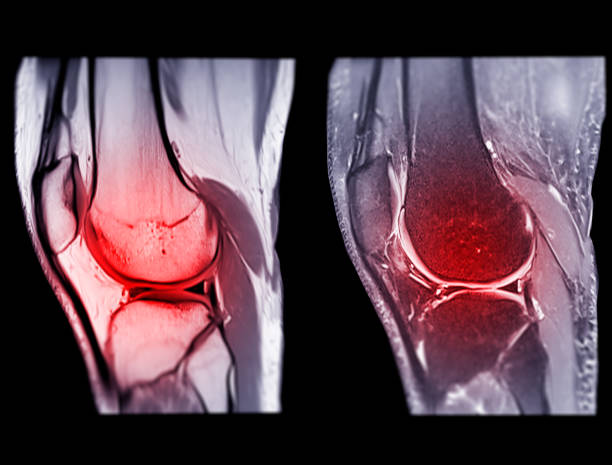

무릎 연골판 손상을 진단하기 위해서는 주로 MRI 검사가 사용됩니다. X-레이 검사는 뼈 위주로 나오기 때문에 연골 손상을 정확하게 확인하기 어렵습니다.